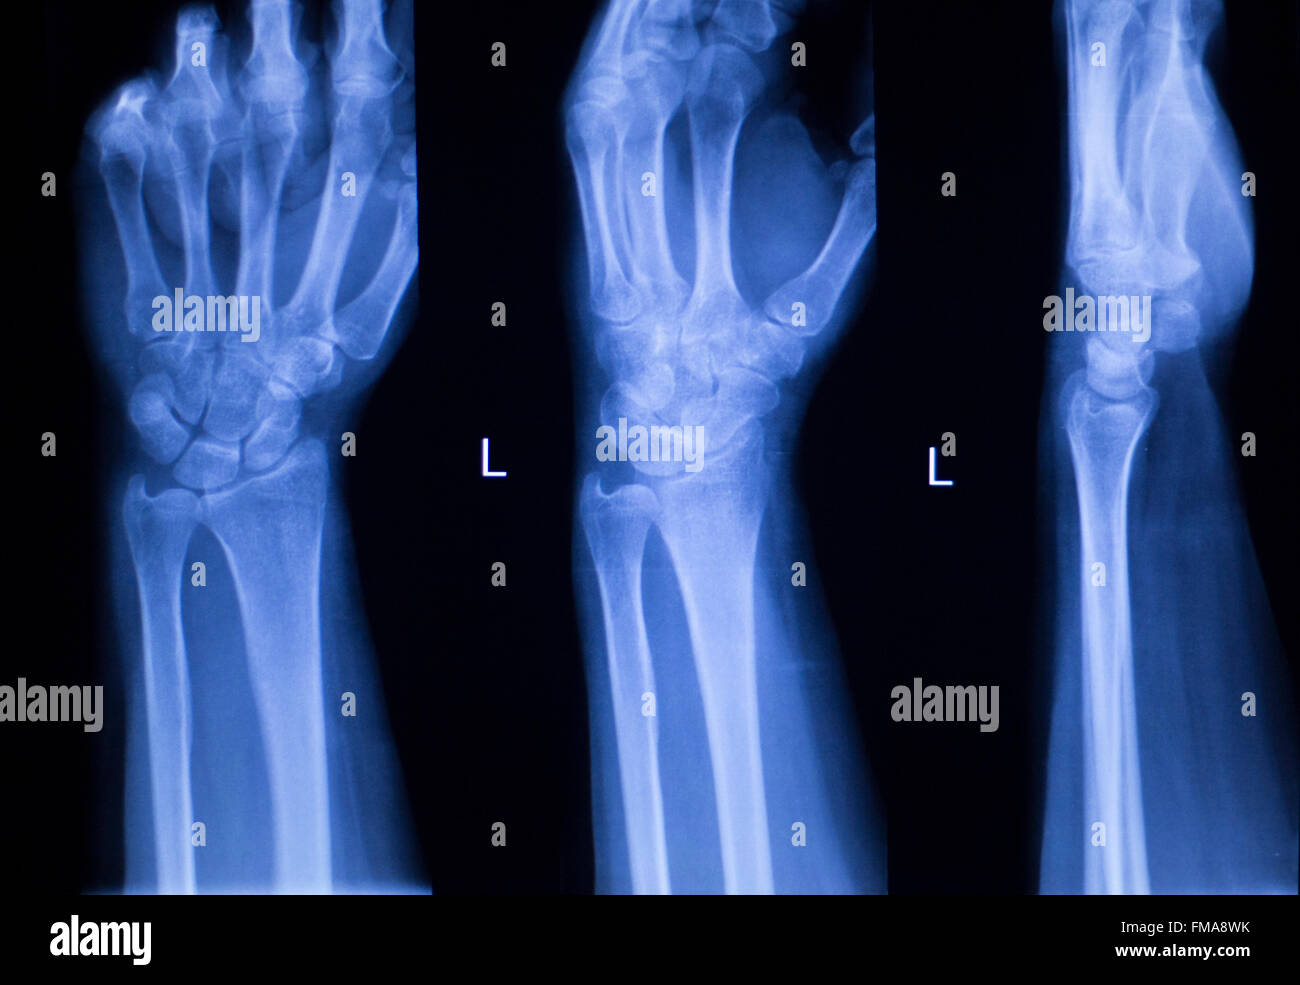

From www.alamy.com

Hand, fingers, thumb and wrist injury orthopedic Traumatology medical x Wrist Injury Evaluation Subacute and chronic causes of. the wrist is inspected for gross deformity, erythema, and swelling (including focal swelling from a ganglion cyst) and is. using information from the history, key symptoms, and findings from the basic wrist examination, the clinician can. wrist pain is traditionally classified as acute pain caused by a specific injury or as subacute/chronic. Wrist Injury Evaluation.